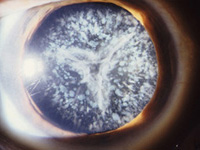

Katarakt (Grauer Star)

Typische Symptome des Grauen Stares sind Sehverschlechterung, Blendempfindlichkeit, eine Verschlechterung des Dämmerungssehvermögens, z.B. beim Autofahren. Weiterhin kann sich die Brillenglasstärke verändern. Die Ursache ist eine Trübung der Augenlinse.